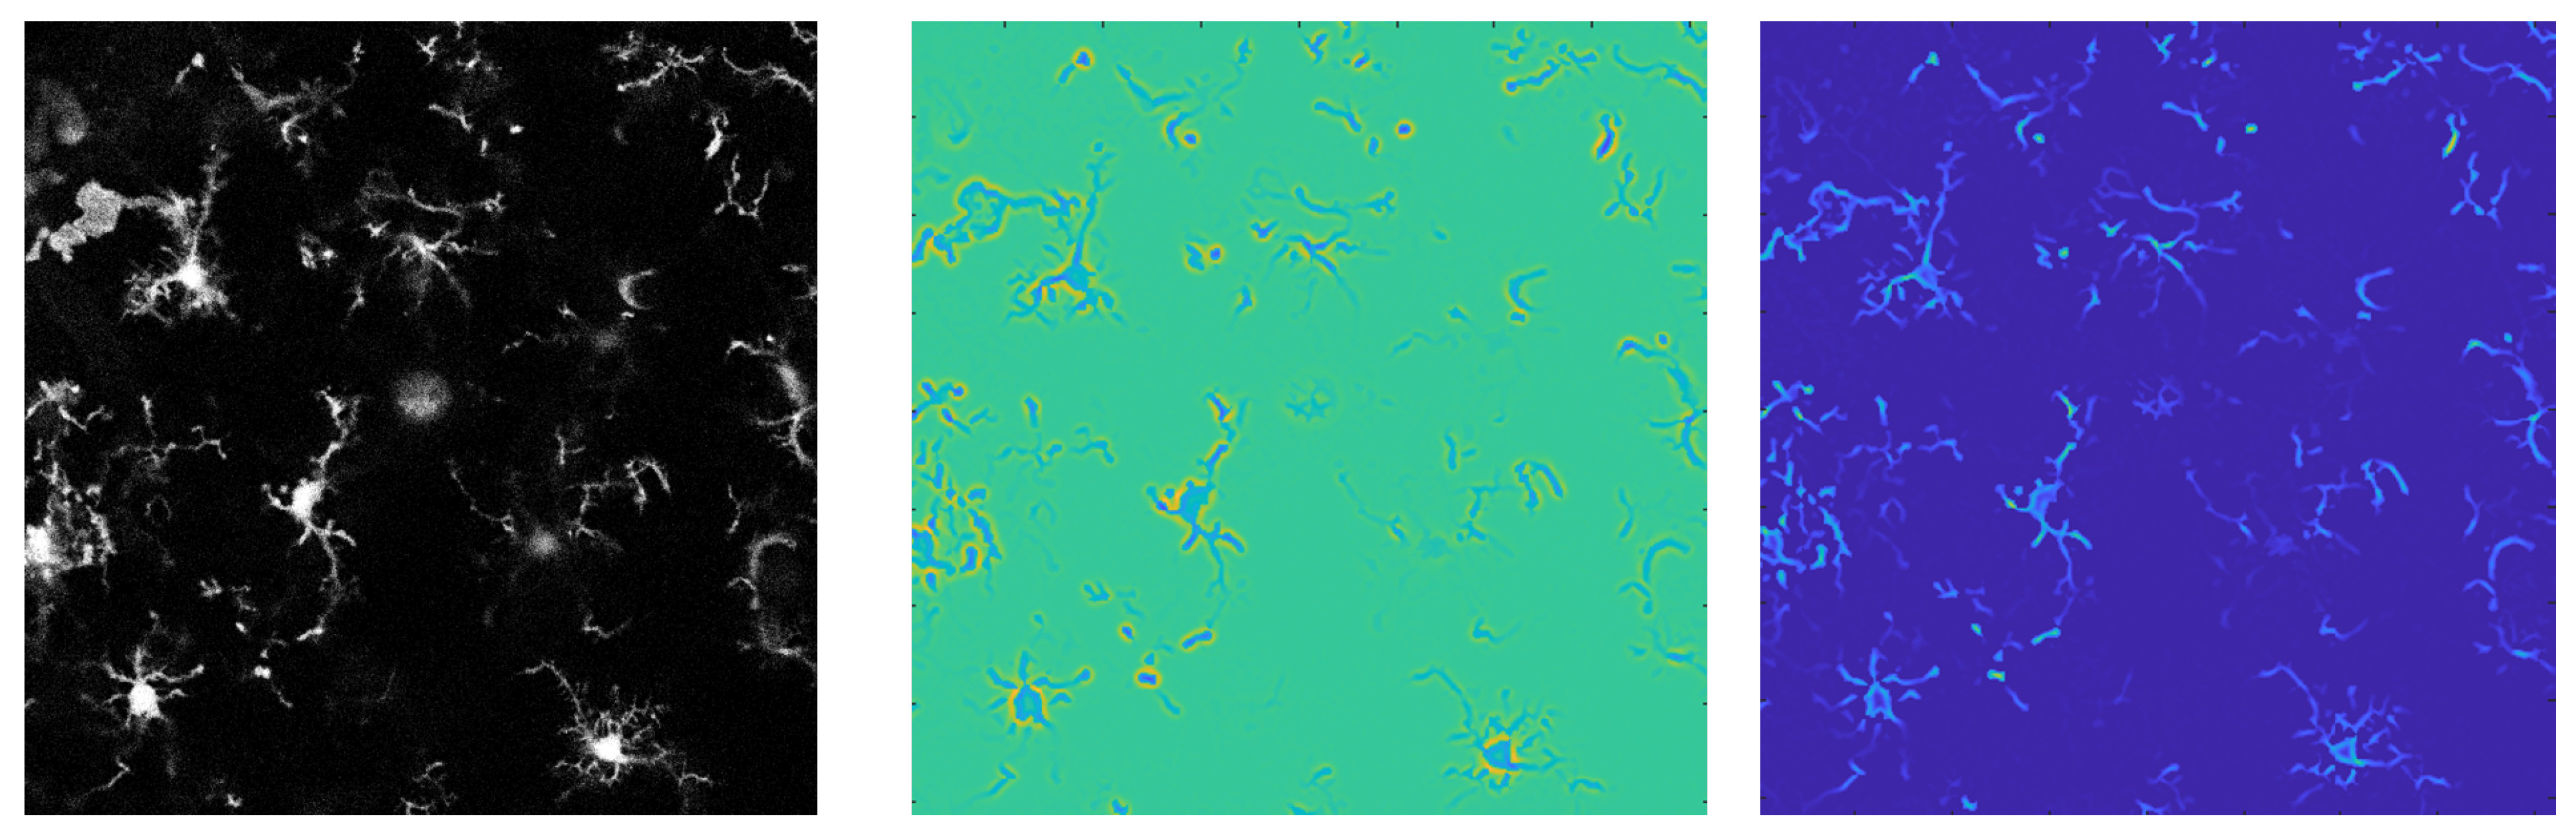

2. Background on Vector Field Convolution

3.3. C3VFC: Tracing Glia in 3D Temporal Images

3.6. Concentric Circles, VFC, Critical Point Detection